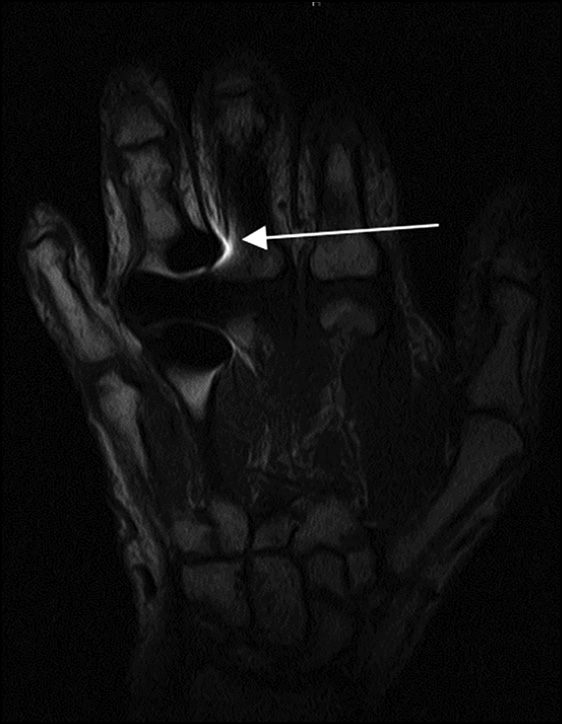

The limitations of the proposed fixation method include the potential inability to use the described splint in patients with contractures or large-space-occupying masses resulting in gross deformation of the contours (Fig. 6). However, in this case, the remaining recommendations should be followed regardless.

Fig. 6. Large encapsulated ganglion cyst of the dorsal hand with neck-like connection to the wrist cavity; (a) PD-weighted images with fat suppression in the axial plane; (b) PD-weighted images with fat suppression in the coronal plane; (c) T1-weighted images in the coronal plane; (d) PD-weighted images with fat suppression in the sagittal plane.